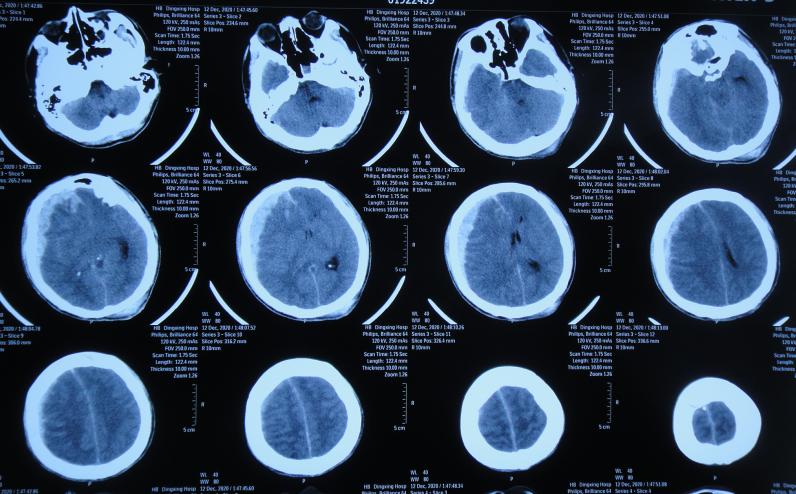

患者于2020年12月12日,在工作时意外从货车上摔下致头颅受伤,出现意识不清,送至河北省定兴县某医院,急诊查头颅CT示颅内血肿,中线有偏移( 图-1 ),给予开颅颅内血肿清除术+去骨瓣减压术,留置引流管,并行气管切开术;术后当天查头颅CT示开颅术后状态( 图-2 ),转入ICU病房。

图-1: 2020年12月12日头颅CT